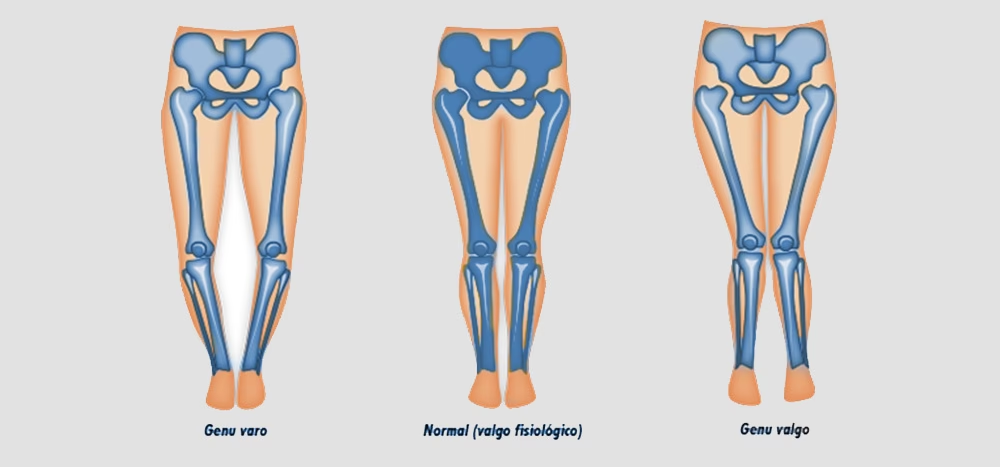

El término médico Genu Valgo describe una deformidad angular de las extremidades inferiores donde el muslo (fémur) y la espinilla (tibia) se desvían hacia afuera en relación con la rodilla, haciendo que las rodillas se toquen mientras los tobillos se mantienen separados. Esta configuración es muy común en la infancia y, en la mayoría de los casos, es una variación fisiológica que se corrige espontáneamente con el tiempo a medida que el niño crece y sus huesos maduran.

El Desarrollo Normal y la Corrección Espontánea

La evolución del Genu Valgo en la infancia sigue un patrón predecible. Después del nacimiento, los bebés suelen presentar un Genu Varo (piernas arqueadas o en 'O'), que gradualmente se endereza. Alrededor de los 2 años, las piernas tienden a alinearse, y entre los 3 y 5 años, es cuando el Genu Valgo se hace más evidente. A partir de los 5 años, y de manera progresiva hasta los 7 años, esta postura en valgo suele ir disminuyendo. Al alcanzar los 7 años, la alineación final de las rodillas tiende a ser un discreto valgo, considerado la posición definitiva y normal en la mayoría de los adultos.